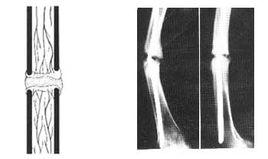

原始骨痂形成或骨內膜和骨外膜的成骨細胞增生,在骨折端內、外形成的骨組織逐漸骨化,形成新骨,稱為膜內化骨。隨新骨的不斷增多,緊貼骨皮質內在治療骨折時,對這些併發症應以預防為主,如果已經出現則應及時診斷和妥善治療,這樣,大多數併發症都是可以避免或治癒的。外面逐漸向骨折端生長,彼此會合形成梭形,稱為內骨痂和外骨痂。骨折斷端及髓腔內的纖維組織亦逐漸轉化為軟骨組織,並隨軟骨細胞的增生、鈣化而骨化,稱為軟骨內化骨,而在骨折處形成環狀骨痂和髓腔內骨痂。兩部分骨痂會合後,這些原始骨痂不斷鈣化而逐漸加強,當其達到足以抵抗肌收縮及成角、剪力和鏇轉力時,則骨折已達到臨床癒合,在成人一般約需 12 ~ 24 周(人衛版外科學教材第8版最新修改)。此時 X 線片上可見骨折處四周有梭形骨痂陰影,但骨折線仍隱約可見。對骨外膜的損傷均對骨折癒合不利。

原始骨痂中新生骨小梁逐漸增加,且排列逐漸規則和緻密,骨折斷端經死骨清除和新骨形成的爬行代替而復活,骨折部位形成骨性連線。這一過程一般約需 1~2 年。隨著肢體活動和負重,應力軸線上的骨痂不斷得到加強,應力軸線以外的骨痂逐漸被清除,並且骨髓腔重新溝通,恢復骨的正常結構 ,最終骨折的痕跡從組織學和放射學上完全消失。

骨痂辨別